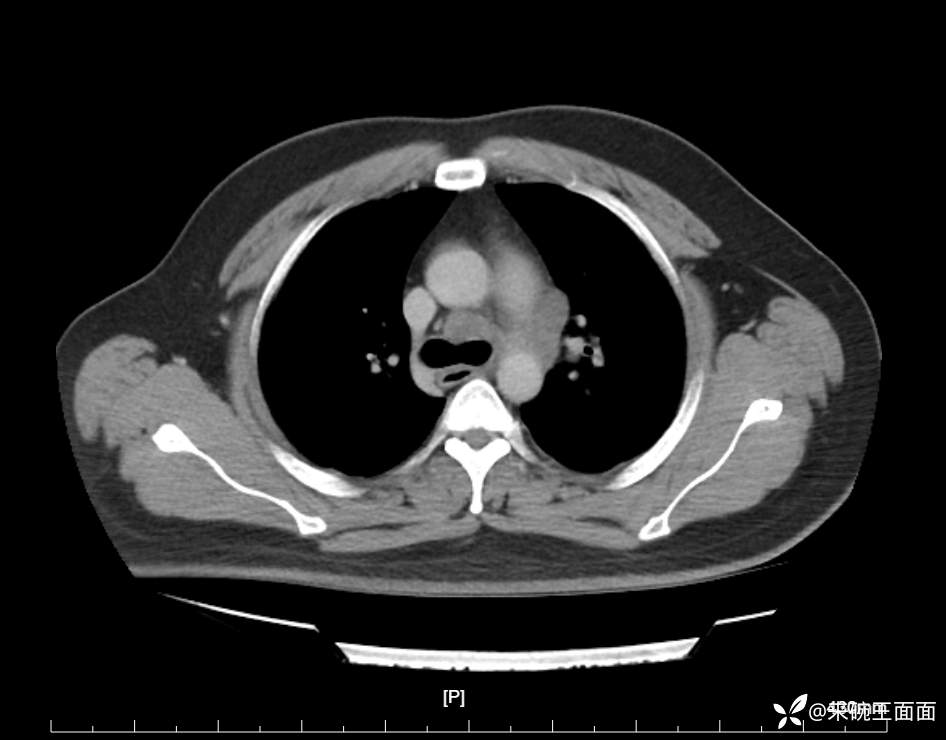

性别:男

年龄:27岁

主诉:胸闷胸痛数月余,休息后可自行缓解,无咯血症状。

个人史:数年吸烟史,具体不详。